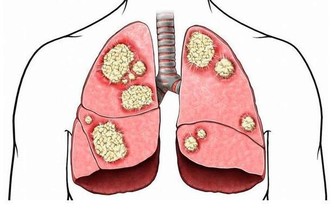

患有鼻炎、鼻竇炎、扁桃體炎等上呼吸道疾病,則會散發出一股腥臭味。

有胃潰瘍、胃炎、胃食管反流等毛病,胃裡消化發酵的氣體排到了口腔裡,則表現為酸臭味。

糖尿病患者,由於沒有足夠胰島素分解醣類,會開始分解脂肪來提供能量,分解物之一的酮體濃度增加,就會產生一股爛蘋果味。

而尿騷味,則通常提示腎有問題了。